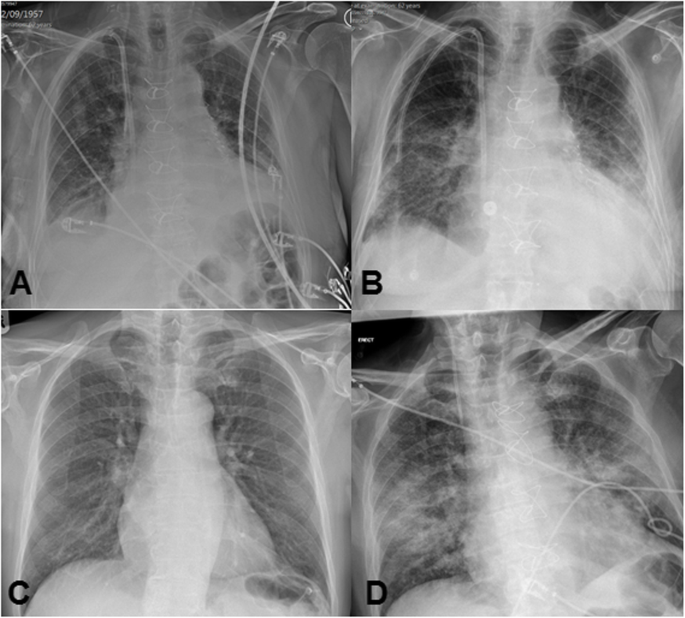

A 62-year-old gentleman presented to hospital with increasing chest pain and shortness of breath during renal replacement therapy at his local dialysis centre. His past medical history was significant for end stage renal failure secondary to nephrotic syndrome, hypertension and diabetes mellitus. He was completely independent at home with daily activities prior to admission. Coronary angiography revealed multi vessel disease and a transthoracic echocardiogram showed a preserved left ventricular function with no significant valvular abnormalities. Chest roentgenogram revealed evidence of mild pulmonary oedema. Discussion at the joint cardiology and surgical meeting suggested surgical revascularisation would be the preferred treatment option. He was subsequently transferred to our institution for inpatient coronary artery bypass grafting. A standard median sternotomy was performed with cardiopulmonary bypass established between the ascending aorta and right atrium. The left internal mammary artery and long saphenous vein was harvested to perform three coronary bypass grafts. He was transferred to the intensive care unit post-operatively in a stable condition and stepped down to the ward on the second post-operative day with regular renal specialist input. On the 5th post-operative day the patient reported weakness, rigors and was febrile. A COVID-19 PCR-RNA swab test on the 6th post-operative day was confirmed positive. Chest roentgenogram revealed bilateral lower lobe diffuse opacities, significantly worse from the 2nd post-operative day chest roentgenogram (Fig. 1). He developed acute respiratory failure and was not considered a candidate for mechanical ventilation given his co-morbid conditions and the poor outcomes that were being reported at the time. The patient unfortunately died on the 7th post-operative day with the cause of death being respiratory failure secondary to COVID-19.